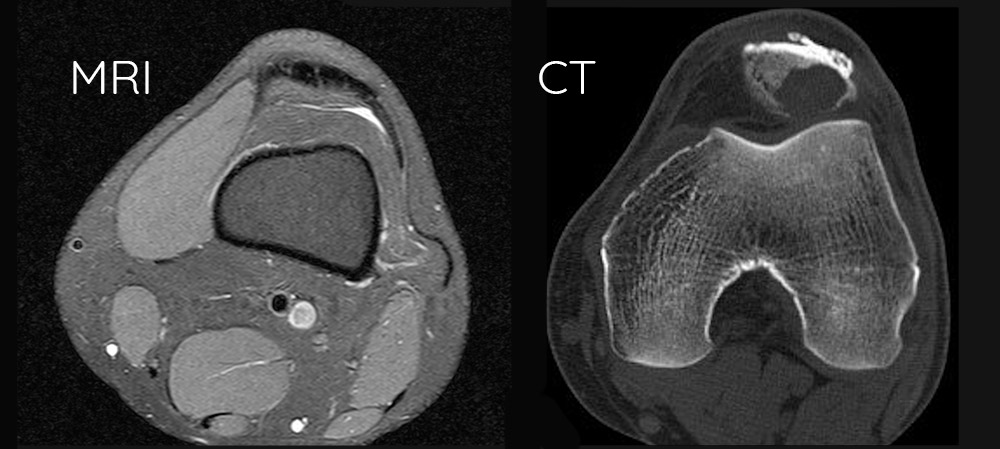

Despite its advantages, CT scanning cannot match MRI’s soft tissue contrast resolution. Brain and spinal cord imaging often requires MRI for detailed evaluation. Cartilage, ligaments, and tendons appear more clearly on MRI examinations.

Each technology provides different information. CT may show bone involvement while MRI reveals soft tissue extent of the same condition.

CT scans provide exceptional bone detail that MRI cannot match. The technology excels at detecting fractures, bone infections, and structural abnormalities within skeletal systems. Small hairline fractures often invisible on MRI become clearly visible through CT imaging.

Bone tumors appear with greater clarity on CT scans, allowing doctors to assess tumor density and calcification patterns. Joint replacements and orthopedic hardware show up clearly without the signal interference that can plague MRI examinations.